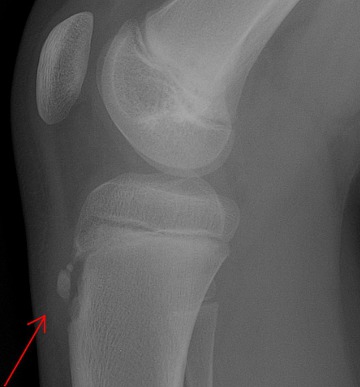

X-ray 검사를 합니다. 성장단계에 따라 크기는 다르지만 경골조면 즉 무릎의 바로 아래에 국한된 골단핵 변화, 유리골편이라는 것이 보여집니다. MRI검사를 하면 연골부를 덮고 있는 슬개건이 두꺼워져 있거나 주변 염증성 변화를 확인할 수 있습니다. 초음파로도 돌출된 뼈와 인대 비후도 볼 수 있습니다.